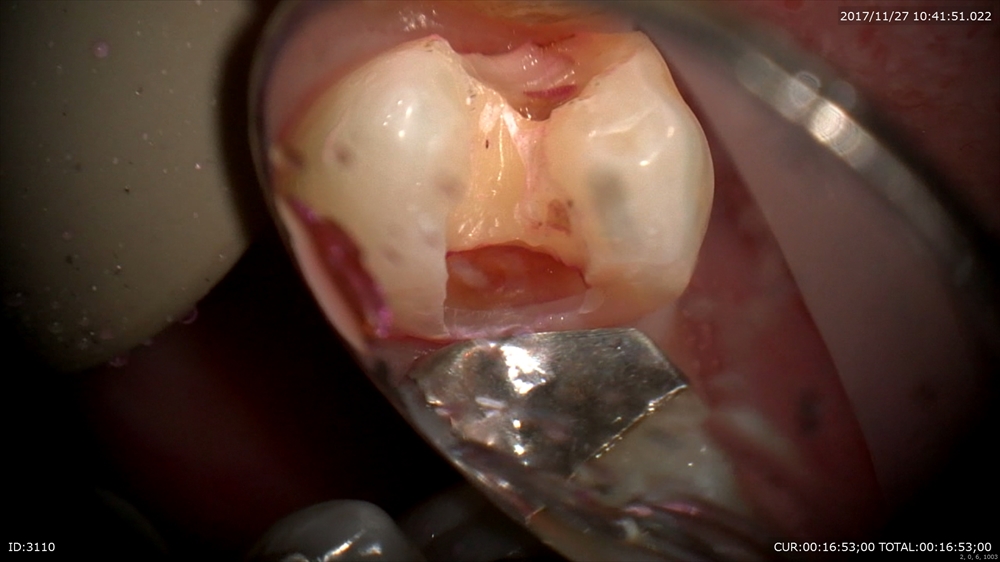

歯科ドックで内部虫歯が発覚!こんなに大きく神経に近い。マイクロスコープで丁寧に。

神経を保護(MTAセメント)

修復。

術前(右)術後(左)金属を使わない治療は健康にも良いです。